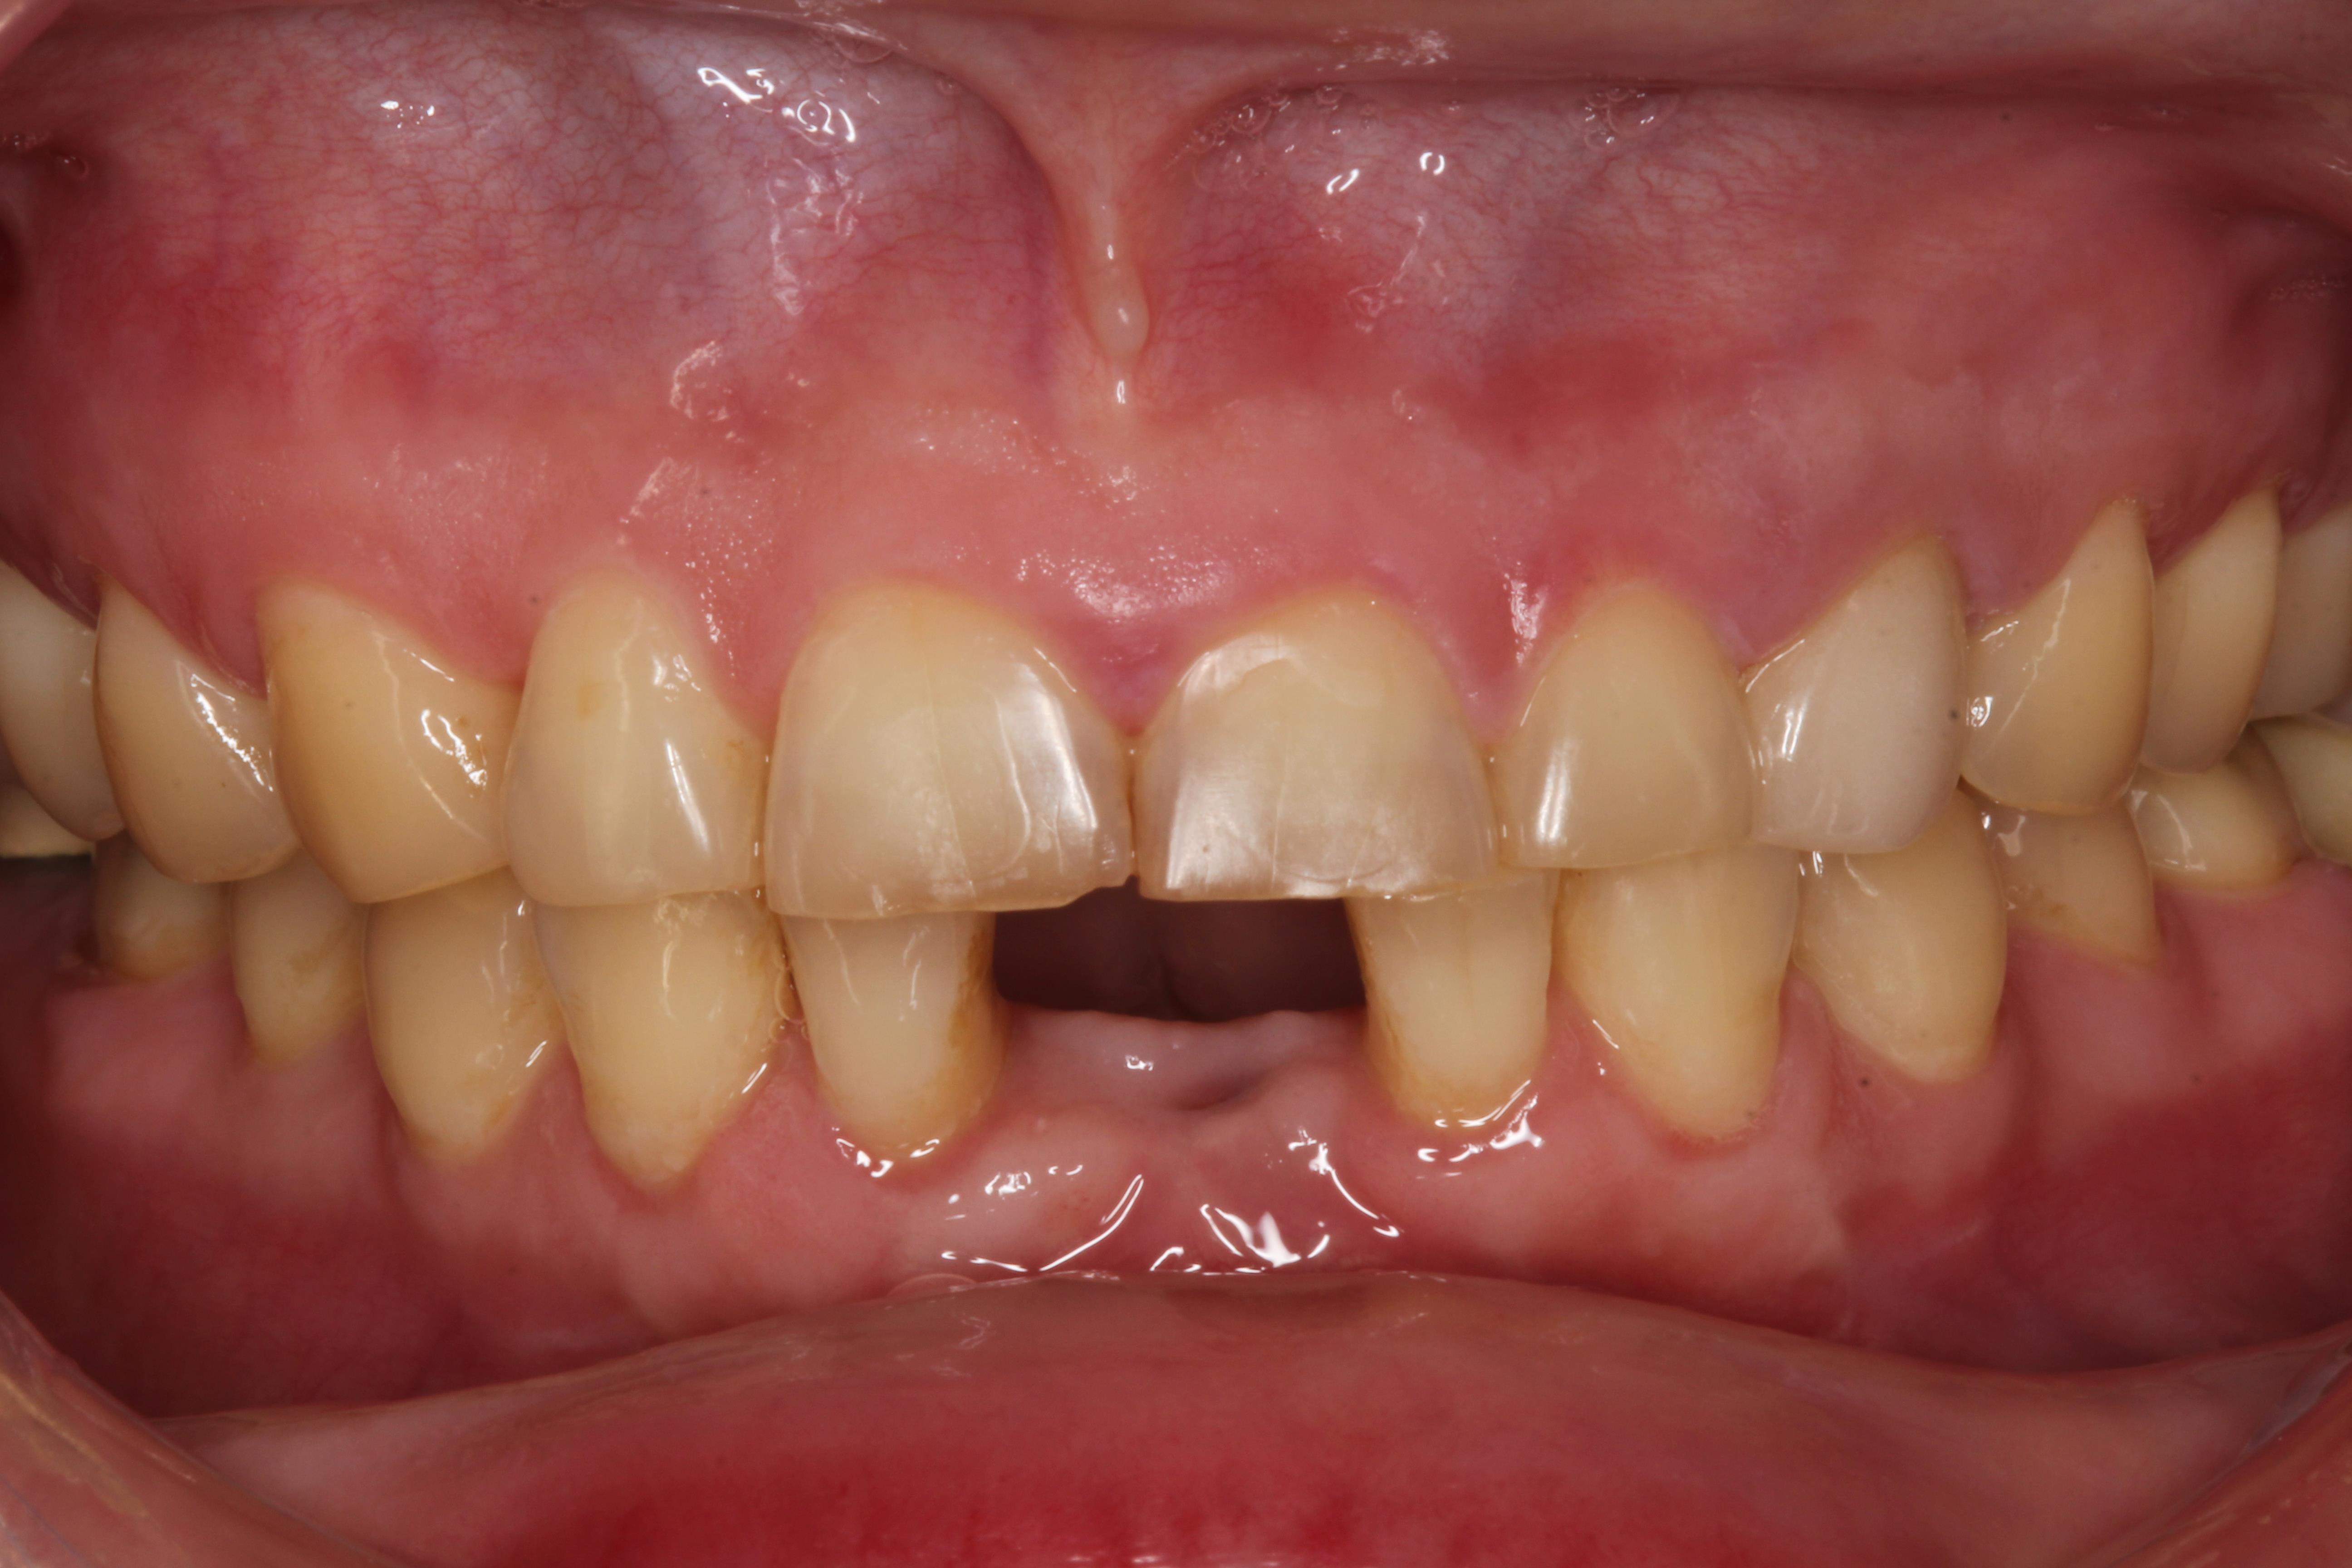

嚴重缺牙的後果? 不管是蛀牙導致的缺牙、退化所致的缺牙、意外造成的缺牙,嚴重缺牙最先會面臨到的問題是「營養流失」,長時間無法正常咀嚼、進食,吸收不佳的情況下,會導致營養不良。 此外,嚴重缺牙會讓口腔上下顎,無法對襯咬合,導致嘴巴無法正常閉合,除了影響美觀,長久下來,也會影響顳顎關節(temporomandibular joint)、咀嚼呼吸系統。 長時間缺後牙的後果? 「缺後牙沒有關係阿,反正看不到,用前面的牙齒咬就好」。這真的是大錯特錯的觀念,長時間缺後牙、錯失黃金治療期,後果,並非想像中的那麼簡單! 「上方後牙區缺牙」,會造成下顎後牙的牙齒往上移,導致錯位咬合,牙脊高度流失、上顎鼻竇腔膨大下墜。之後如果要植牙時,必須伴隨補骨、牙脊增高術或者上顎竇增高術。 「下方後牙區缺牙」,會造成上顎後牙的牙齒往下墜,導致錯位咬合,錯失黃金治療期,會讓牙脊高度、寬度流失,導致缺牙區沒有空間做假牙。 - 假牙的種類 2026.01.19